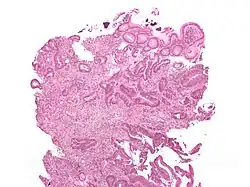

O tipo do tumor é geralmente diagnosticado através da análise de tecido removido através de uma biópsia ou cirurgia. O diagnóstico patológico geralmente contém a descrição histológica do cancro, e o grau. O tipo mais comum de cancro colorretal é adenocarcinoma, que compõe 95% dos casos - acredita-se que a maioria dos casos de cancro colorretal envolvam tumores originários de pólipos adematosos. Outros tipos, mais raros, de cancro colorretal, incluem linfoma e carcinoma espinocelular. As causas do cancro colorretal não são conhecidas com exatidão no presente.

Adenocarcinoma é um tipo de tumor maligno epitelial, que se origina do epitélio glandular da mucosa colorretal. Tal tumor invade a parede, infiltrando a mucosa muscular, a submucosa, e daí, a muscularis propria. As células do tumor abrigam estruturas tubulares irregulares, de estrutura pluristratificada, lúmens múltiplos, e estromas reduzidos. Por vezes, as células do tumor secretam muco, que invade o fluido intersticial, produzindo grandes agrupamentos de muco e colóide (que, visualmente, aparecem como "espaços vazios") - é o chamado adenocarcinoma colóide, pouco diferenciado. Se o muco permanece dentro da célula do tumor, o muco empurra o núcleo celular para a periferia da célula - célula do tipo signet-ring. Dependendo da arquitetura glaudular, pleomorfismo celular, e padrão da secreção de muco, o adenocarcinoma pode ser categorizado em três graus de diferenciação: bem diferenciado, moderadamente diferenciado, e mal diferenciado.[48]